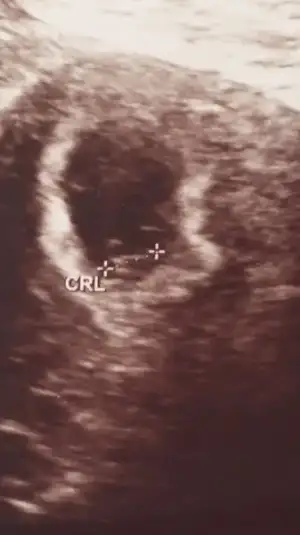

IMG_5220.webp

Merhabalar banada yardımcı olur musunuz? Benimki tüp bebek iki gün önce kontrol vardı gittim ama bizimki dönmedi 8+2 fotosu var sizce nedir cinsiyeti